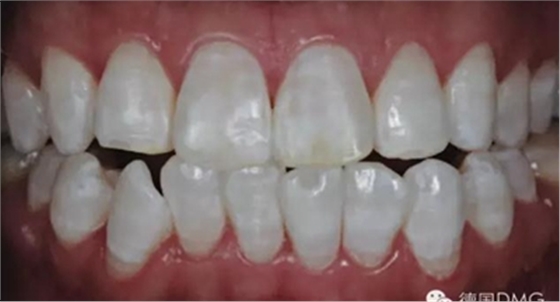

作為日常檢查的一部分,患者強(qiáng)烈要求對(duì)前牙區(qū)的白色斑塊進(jìn)行治療(Fig. 1). 權(quán)衡比較了多種治療方案后, 患者和我們共同選擇了滲透治療。

經(jīng)大量研究和證據(jù)表明,滲透治療是最適合用于牙正畸后由于牙釉質(zhì)脫礦造成的白斑病變。根據(jù)患者的居住地區(qū)和成長經(jīng)歷以及白斑的表現(xiàn)形式,我們將位于牙位11和21的唇面白斑診斷為氟牙癥指數(shù)0.5(根據(jù)Dean的社區(qū)氟牙癥指數(shù)).